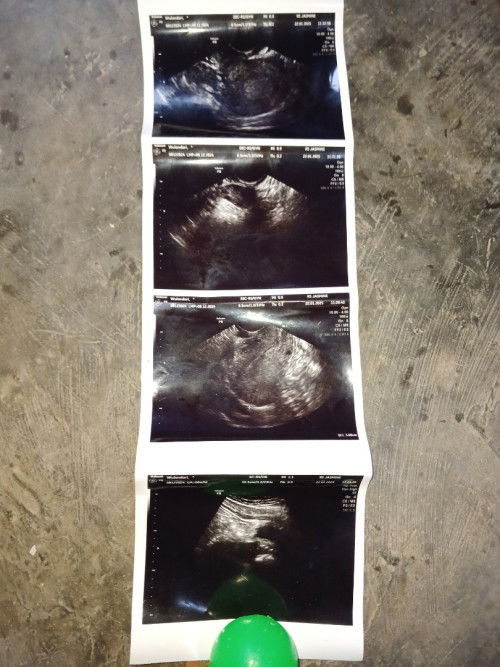

Hpht saya kn 8 Desember ,tgl 11 januari saya TP hasil nya garis 2 samar,stlh itu tgl 18 saya k klinik dktr sruh TP ulang udah garis dua tebal bun dan sdh d nyatakan hamil mau msuk 6minggu saat itu,eh saat tgl 20 saya ngeflek sedkit² tp tidak merasakan sakit kram perut 3 hari dikahamilan 6w3d jdi saya usg ke rs trdkt di usg perut katanya blm kelihatan kantong nya jdi di saran kn usg transvaginal jdi stlh melakukan usg transvaginal doktr tdk blng apa² cuma dia blng blm kelihatan kantong janin nya ajja gt,jdi d sruh kontrol lgi 2 minggu kemudian dan di kasih tespek dri rs ,plng dri rs saya tespek masih garis 2,pas plng dri rs flek nya ini malah agk banyak smpe 3 hari ,Setelah itu saya coba lg buat TP msih jga tetap garis 2,selang 2 minggu kemudian jdwal kontrol saya ,dengan saya belum ada biaya buat kontrol usg lgi saya TP lgi jga msih tetap garis 2 ,jdi saya belum ada lagi kontrol smpe skrg klo menurut hpht udh 10 minggu bun dan di TP msih tetap positif,yang skrg saya mau tanyakan apakah di usia kehamilan 10 minggu ini sdh kelihatan kantong janin nya tdk ya? Soalnya gejala² hamil kyk mual gtu jg udh gk lgi cuma klo mkn itu sering dan milih² jg,apalgi Payudara klo malam smpe pagi bngun tdr gtu sering kencang dan nyeri bun,dan keputihan jg bun#mohonbantujawabbunda #Sharingdong_Bund #bantujawab #firstmom #firsttimemom

Hamil 6 minggu blm kelihatan kantong janin

Dngn keluhan keluar flek darah udh 3 hari keluar darah tpi tdk ada kantong janin,dan dokter pun blng sruh tespek ulang,udh tespek masih positif,dan dngn kluar nya darah 3 hari kata dokter tdk ada tanda² keguguran,jdi di sruh dokter kontrol 2 minggu lagi buat mastiin kantong janin nyaa,tips dong bun buat pereda keluar flek darah nya soalnya dokter cuma kasih obat vitamin elkana saja🙏🏻😊#Sharingdong_Bund #mohonbantujawabbunda #bantujawab #sharing